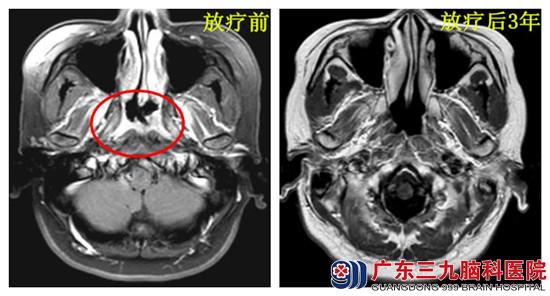

【调强放疗治愈鼻咽癌】

患者朱某,女,33岁,因主诉痰中带血1年余,于2012年1月到广东三九脑科医院就诊入院。患者2009年无明显原因出现痰中带血,无伴视物模糊,无耳鸣,听力下降等,因怀有身孕,自认为呕吐所致,未予重视。2010年10月,患者顺产诞下一婴儿后痰中带血症状消失,12月此现象再次出现,但仍未重视。2011年,患者因出现反复发作的左颈部疼痛,到当地医院检查,行耳鼻喉镜检查发现右侧鼻咽肿物,取活检病理显示:未分化型非角化性癌。鼻咽MR示:右侧鼻咽顶侧壁粘膜较对侧略显增厚,邻近组织结果未见异常表现;双侧颈部动脉间隙偏上部肿大淋巴结。结合患者病史及影像学检查,临床分期:鼻咽癌II期(T2N0M0);于2012年1月-3月于广东三九脑科医院行鼻咽肿物调强放疗,过程顺利。目前已随访3年,未见肿瘤复发。